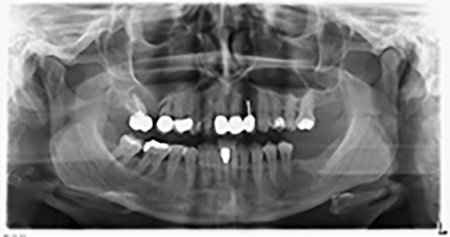

About six months after teeth 16 and 14 were extracted, a digital volume tomography (DVT, Planmeca) examination was performed for planning and risk minimization purposes. It clearly showed that the bone had not regenerated to the desired volume (Fig. 2 to 7).

A sinus floor elevation was required in both regions 16 and 14 to guarantee a fixed restoration based on at least two implants. Relatively large-scale bone augmentation was required due to the residual bone volume being extremely low in this case. Major bone augmentation procedures are invasive and linked to higher patient morbidity, as well as being time-consuming and expensive. It is more difficult to predict the results of the treatment and the risk of failure is increased. The patient was informed of the increased risk and was offered a removable solution, which she consistently rejected.

To restrict the augmentation to region 14, and in consultation with the patient, it was planned that implant 16 would be placed, inclined, in the dorso-cranial direction (Fig. 8).